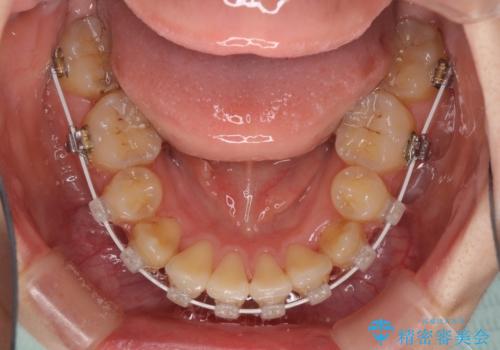

- 審美装置

- 2年10ヶ月

- 10-30回

結婚式の予定があったため、まずは前歯をきれいに整えるようにしました。

結婚式の時には一時的に前歯の装置を外し、口元を気にせず笑える結婚式を迎えることができました。